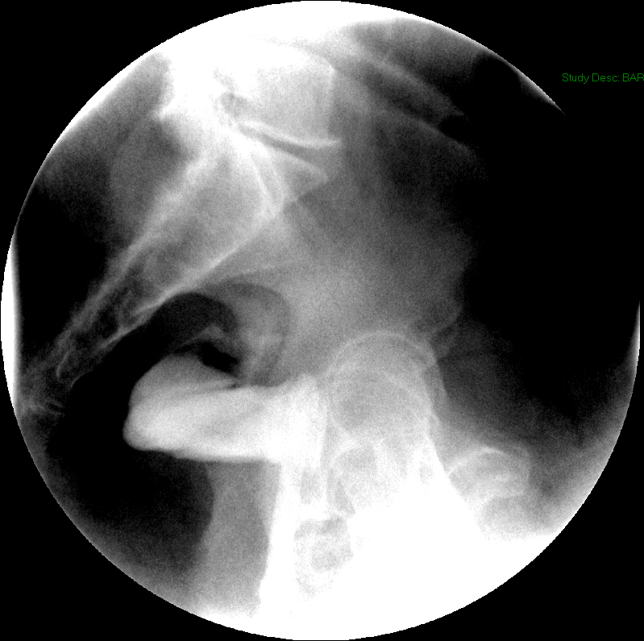

- After the enema tip has been placed but before contrast material has been administered, obtain a fluoroscopic spot film of the rectum with the patient in the left lateral position

(key image 33).

- As you instill contrast material into the J pouch, obtain images of the pouch and ileoanal anastomosis fully distended with contrast material in each of the following four (4) positions:

- left lateral

(key image 34)

- left posterior oblique

(key image 35)

- supine (AP)

(key image 36)

- right posterior oblique

(key image 37).